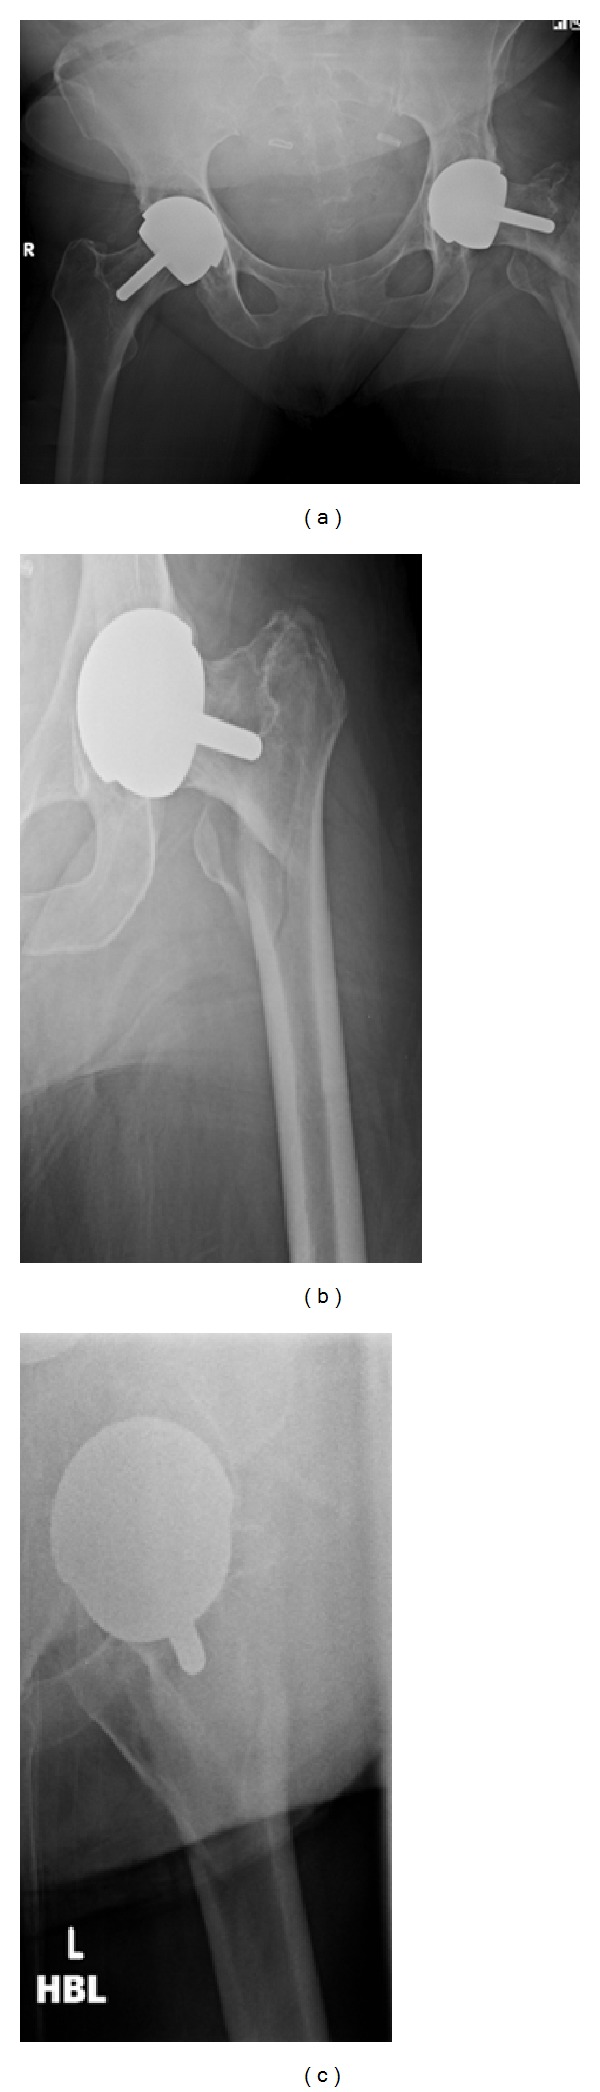

A 56-year-old lady presented to hospital after a fall onto her left hand side, after which she was unable to weight bear. On examination her leg was shortened, externally rotated, and neurovascularly intact. There was a history of previous bilateral Birmingham hip resurfacing (Smith & Nephew) with the left side five years prior to admission and the right side one year before. Other past medical history included, osteoarthritis affecting hands, hips, knees and spine, as well as hypertension and diet controlled type 2 DM. There had also been a recent history of increased alcohol consumption. A pelvic X-ray taken in 2007 demonstrated significant bilateral hip osteoarthritis. Figure 1 shows a radiograph from 2009 after her right hip resurfacing and prior to surgery on the left. Figure 2 demonstrates the injury sustained in early December 2012.

Figure 1.

Pelvis radiograph from 2009.

Figure 2.

(a) and (b), AP views. (c) Lateral view.